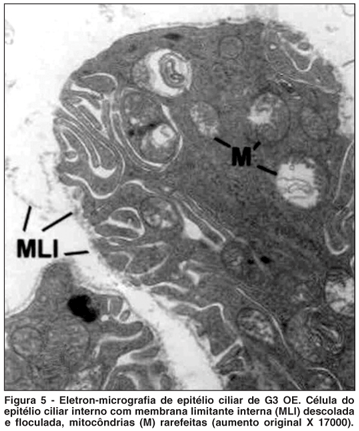

OE - Maleato do timolol (Figura 5)

Nos olhos deste grupo observaram-se células com aspecto retraído e membrana limitante interna descolada e floculada. Foram observados também: alargamento e diminuição das invaginações, assim como figuras de mielina entre invaginações. As mitocôndrias apresentaram rarefação e figuras de mielina no seu interior.

No citoplasma observaram-se corpos densos e vesículas claras em grande quantidade. Foi observada liberação de material citoplasmático.